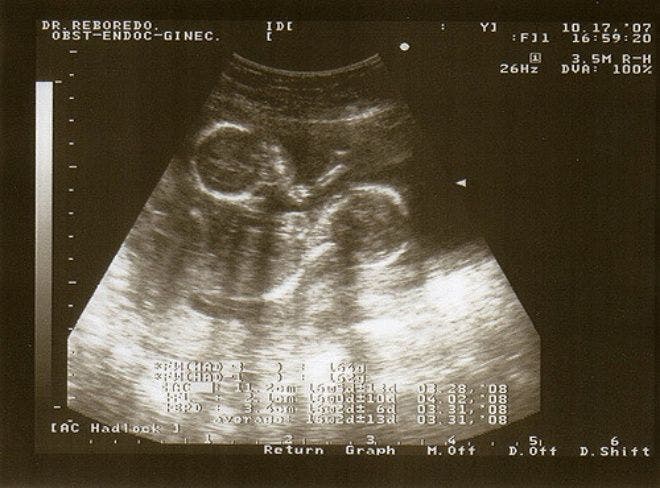

Aux yeux des médecins, les jumelles n’allaient probablement pas survivre à la grossesse. En cause, une maladie rare qui se caractérise par l’enchevêtrement de leurs cordons ombilicaux. L’image peut choquer et en étonner plus d’un et s’inscrit dans la liste succincte des jumelles les plus étonnantes (à l’instar du cas Abby et Brittany Hensel, des jumelles qui partagent le même corps).

Kate avait déclaré que les jumelles étaient très proches et ont été vues dans l’utérus dormir côte à côte et main dans la main.

Les photos de l’échographie sont comme l’exprime Kate « incroyables » pour les yeux. « Deux corps enroulés l’un autour de l’autre dans un câlin ferme. Deux visages se regardant dans les yeux. Nous avions hâte de voir nos filles partager ce lien », a poursuivi la maman.

À 28 semaines de grossesse, Kate a été admise à l’hôpital pour les analyses et contrôles quotidiens avant de procéder à une césarienne qui était prévue à 32 semaines. Ses filles pesaient 1,9 kg et 1,5 kg mais les médecins ont été surpris de réaliser l’enchevêtrement étonnant des cordons.